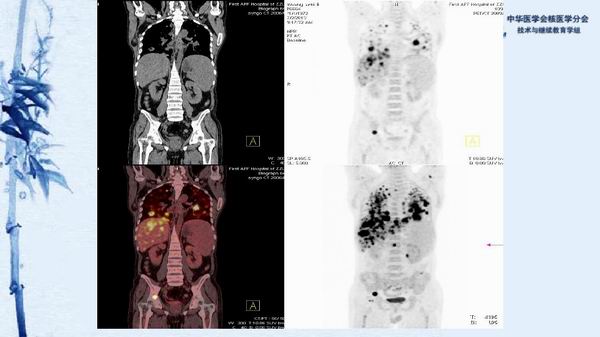

病例49:PET-CT显像诊断淋巴瘤相关噬血细胞综合征一例-【CSNM继教学组】程兵 郑州大学第一附属医院